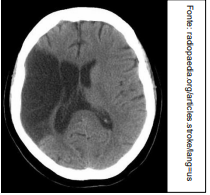

Um médico está atendendo Laura, estudante que retorna às aulas após internação recente em UTI por acidente vascular cerebral (AVC). No relatório de alta, consta que ela apresentou AVC tipo Hemorragia Subaracnoide Aneurismática, e há uma cópia da tomografia computadorizada de crânio, sem contraste, realizada pela paciente na admissão. A imagem que melhor corresponde ao achado do exame de imagem de Laura é: